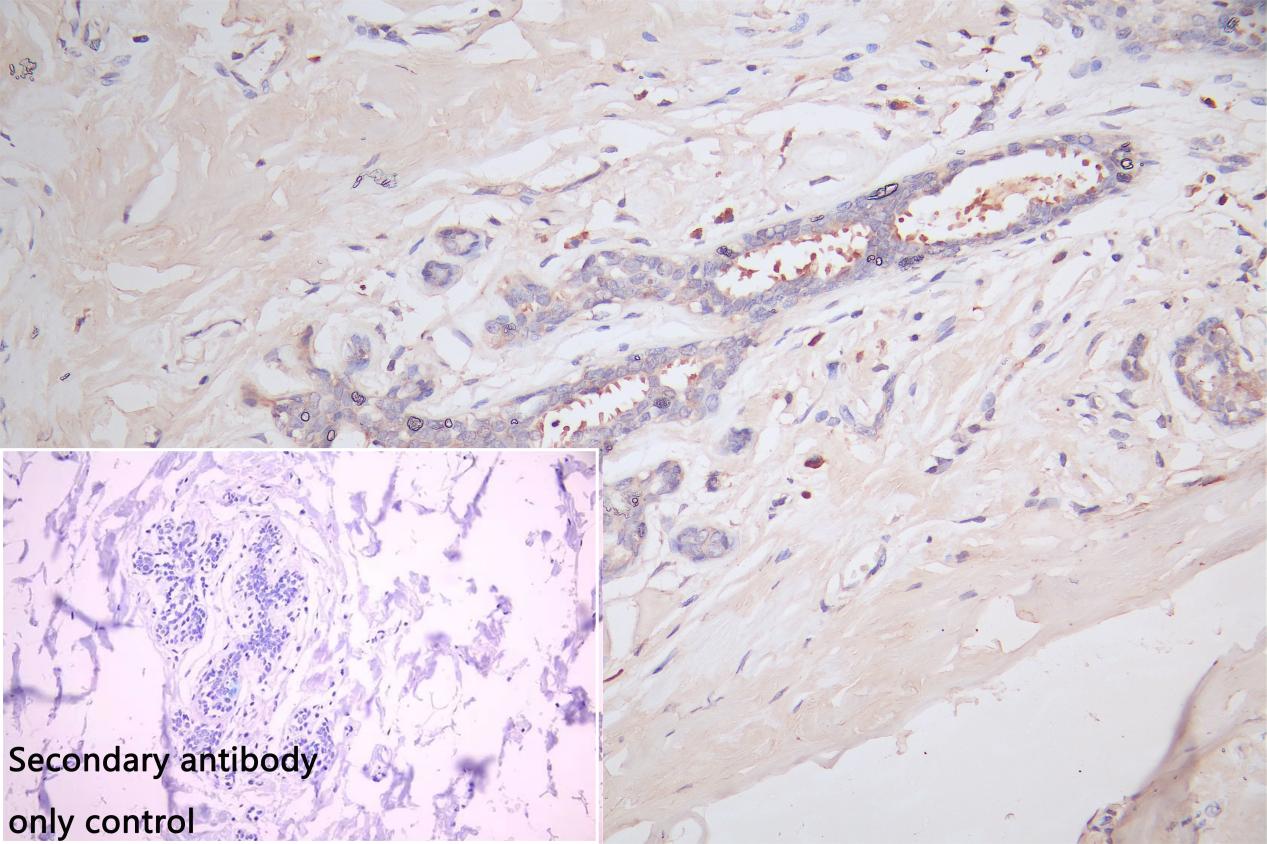

IHC image of CSB-PA011621ESR1HU diluted at 1:66 and staining in paraffin-embedded human breast cancer performed on a Leica BondTM system. After dewaxing and hydration, antigen retrieval was mediated by high pressure in a citrate buffer (pH 6.0). Section was blocked with 10% normal goat serum 30min at RT. Then primary antibody (1% BSA) was incubated at 4°C overnight. The primary is detected by a Goat anti-rabbit polymer IgG labeled by HRP and visualized using 0.05% DAB. Secondary antibody only control: uses 1% BSA instead of primary antibody